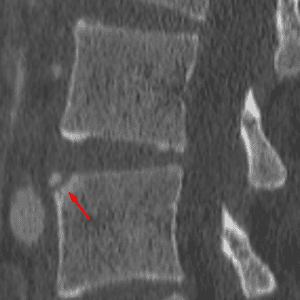

Limbus Vertebra

Mimicking a fracture